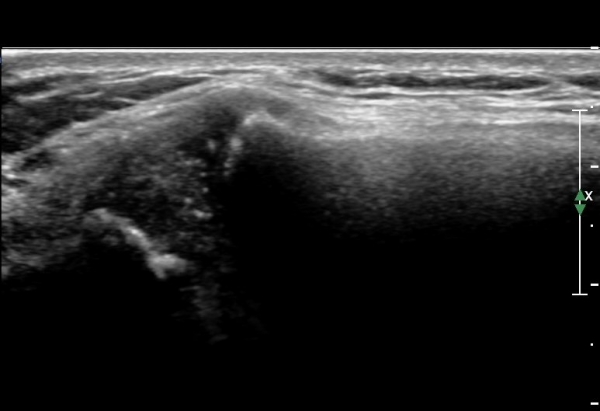

ÁÂÃø Èä°ñ¼â°ñ°üÀýÃÊÀ½ÆÄ°Ë»ç¿¡¼­ ƯÀÌ ¼Ò°ßÀ» º¸ÀÌÁö ¾ÊÀ½(»çÁø 1, 2).